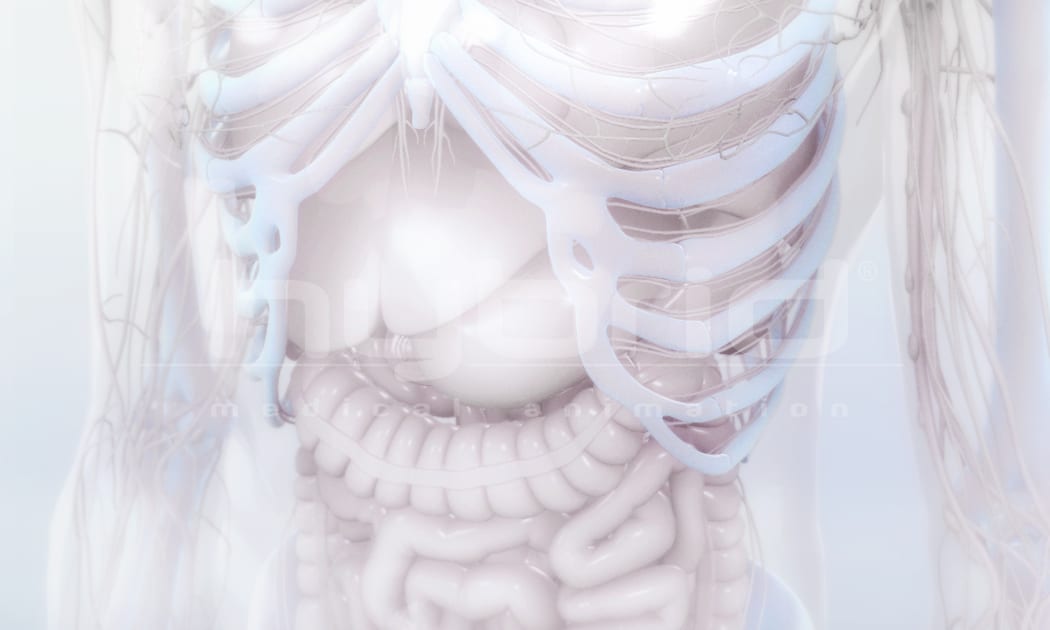

Sometimes we are called upon to bring the complexity and beauty of the human body into a clean, stylized, white “world.”

This is an example of that approach.

Color accents are often added to compliment the story or highlight key components.